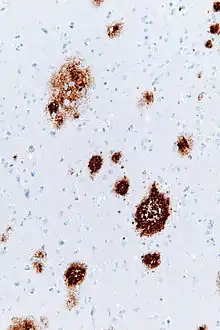

Amyloid plaques (also known as neuritic plaques, amyloid beta plaques or senile plaques) are extracellular deposits of the amyloid beta (Aβ) protein mainly in the grey matter of the brain.[1][2][3][4] Degenerative neuronal elements and an abundance of microglia and astrocytes can be associated with amyloid plaques. Some plaques occur in the brain as a result of aging, but large numbers of plaques and neurofibrillary tangles are characteristic features of Alzheimer's disease.[5] Abnormal neurites in amyloid plaques are tortuous, often swollen axons and dendrites. The neurites contain a variety of organelles and cellular debris, and many of them include characteristic paired helical filaments, the ultrastructural component of neurofibrillary tangles.[3] The plaques are highly variable in shape and size; in tissue sections immunostained for Aβ, they comprise a log-normal size distribution curve with an average plaque area of 400-450 square micrometers (µm²). The smallest plaques (less than 200 µm²), which often consist of diffuse deposits of Aβ,[4] are particularly numerous.[6] The apparent size of plaques is influenced by the type of stain used to detect them, and by the plane through which they are sectioned for analysis under the microscope.[4] Plaques form when Aβ misfolds and aggregates into oligomers and longer polymers, the latter of which are characteristic of amyloid.[7] Misfolded and aggregated Aβ is thought to be neurotoxic, especially in its oligomeric state.[8]

Amyloid plaques are visible with the light microscope using a variety of staining techniques, including silver stains, Congo red, Thioflavin, cresyl violet, PAS-reaction, and luminescent conjugated oligothiophenes (LCOs).[32][4][33] These methods often stain different components of the plaques, and they vary in their sensitivity[4][34] Plaques may also be visualized immunohistochemically with antibodies directed against Aβ or other components of the lesions. Immunohistochemical stains are especially useful because they are both sensitive and specific for antigens that are associated with plaques.

The Aβ deposits that comprise amyloid plaques are variable in size and appearance.[3][4] Under the light microscope, they range from small, wispy accumulations that are a few microns in diameter to much larger dense or diffuse masses. So-called 'classical plaques' consist of a compact Aβ-amyloid core that is surrounded by a corona of somewhat less densely packed Aβ.[4] Classical plaques also include abnormal, swollen neuronal processes (neurites) deriving from many different types of neurons, along with activated astrocytes and microglia.[3][4] Abnormal neurites and activated glial cells are not typical of most diffuse plaques, and it has been suggested that diffuse deposits are an early stage in the development of plaques.[35]